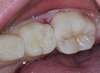

Lorsqu'il y a une perte de substance soit liée à une carie soit à un problème d'émail (MIH), on pourra réaliser une petite "pièce de puzzle" en composite ou céramique fabriquée au laboratoire de prothèse et collée ensuite sur la dent pour remplacer la perte de substance. On restaure ainsi l'esthétique et la fonction masticatoire de la dent.